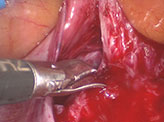

At laparoscopy, the bowel was seen densely adherent to both adnexa, making it difficult to visualize the adnexa. Bowel (rectosigmoid) was adherent to the posterior surface as well as fundus of the uterus.

The bowel adhesions near the left adnexa were released by sharp dissection. Bowel adhesiolysis could be only done partially since there was a high risk of bowel injury. At one point, tissue resembling chorionic tissue was seen projecting out from a structure resembling the fallopian tube. Tube could not be identified separately. Chorionic tissue was taken for histopathological examination. Bleeding points were identified from the suspected base of the tube, which was coagulated using microbipolar cautery. Since the vital structures like ureter and iliac vessels were extremely close to the lateral wall, further coagulation of the bleeding points could not be done. Drain was inserted and patient was followed up with serial βhcg. 4 days after the surgery, decreased to 3110 mIU/ml. The following week the value was 526 mIU/ml. She was followed up with expectant management with serial weekly monitoring of βhcg. The value reached negligible limits 5 weeks after surgery.